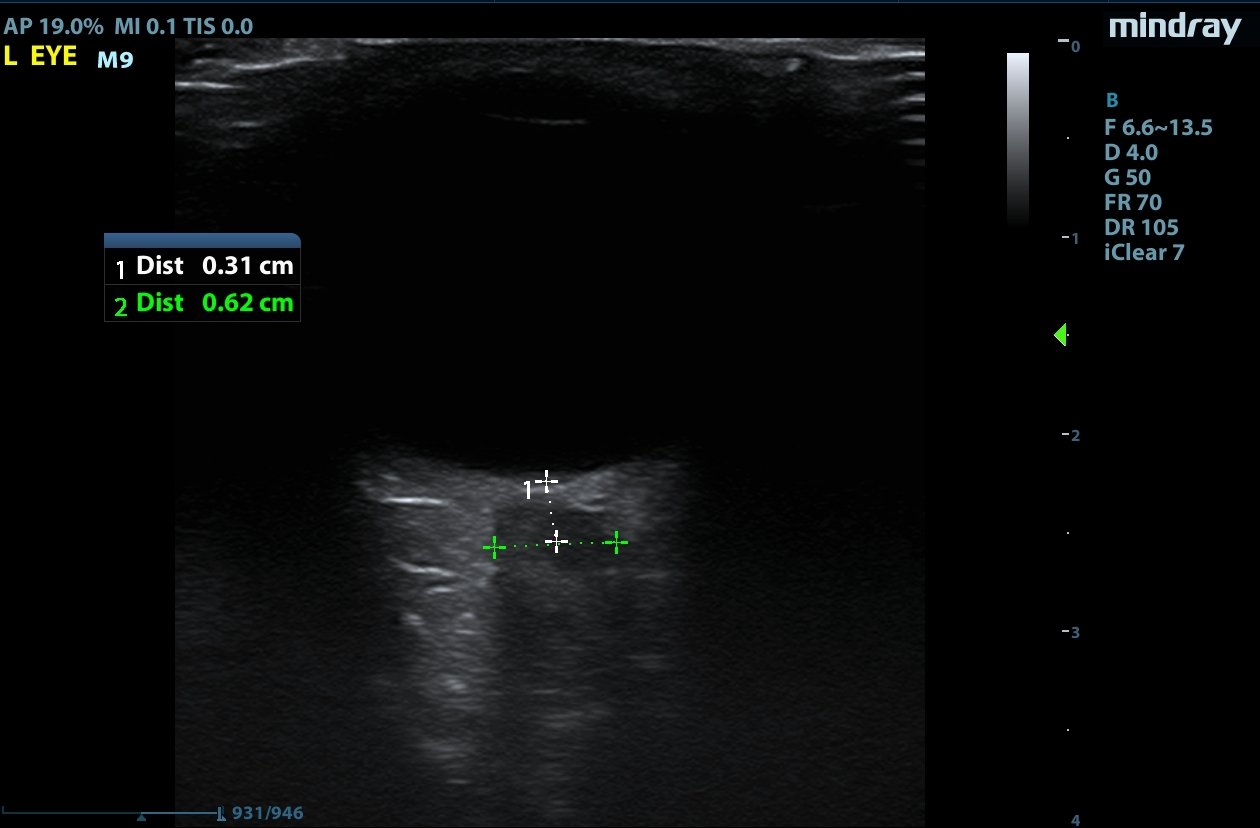

Optic nerve sheath diameter (ONSD) was measured via ultrasound with diameter 5.7mm on left and 6.2mm on right. In order to measure ONSD via optic ultrasound the high-frequency linear array probe (7.5-10-MHz or higher) is utilized in B-mode. The patient is positioned supine and an occlusive dressing, such as Tegaderm, is placed over a closed eyelid with copious conductive gel on top of the dressing. Being careful not to put pressure on the globe, an axial cross-sectional image of the globe is obtained. As demonstrated in the image “annotated left eye ONSD pre-lumbar puncture,” there are two main anechoic areas of the globe, the anterior chamber and the vitreous humor. These anechoic structures are separated by the hyperechoic iris, which surfaces the hyper-echoic-lined lens. At the back of the vitreous humor is the retina, which leads posteriorly into the optic nerve. The optic nerve is the hypoechoic structure posterior to the retina and surrounded by the hyperechoic subarachnoid space, which is encased by the hypoechoic dura mater. The outer edge of the hypoechoic dura matter is where the ONSD is measured.1 The user applies calipers to measure 3mm perpendicularly behind the retina along the hypoechoic optic nerve, and at this level the transverse dimensions of the ONSD are measured using calipers as shown in the images.

Computed tomography (CT) of the head was performed and showed no abnormalities. Lumbar puncture was performed in left lateral decubitus position revealing elevated opening pressure of 29cm H2O. Thirty-five mL of clear cerebral spinal fluid was drained and was negative for all infectious studies.  Optic nerve sheath diameter was again measured post-lumbar puncture with diameters 5.4mm on left and 5.4mm on right.